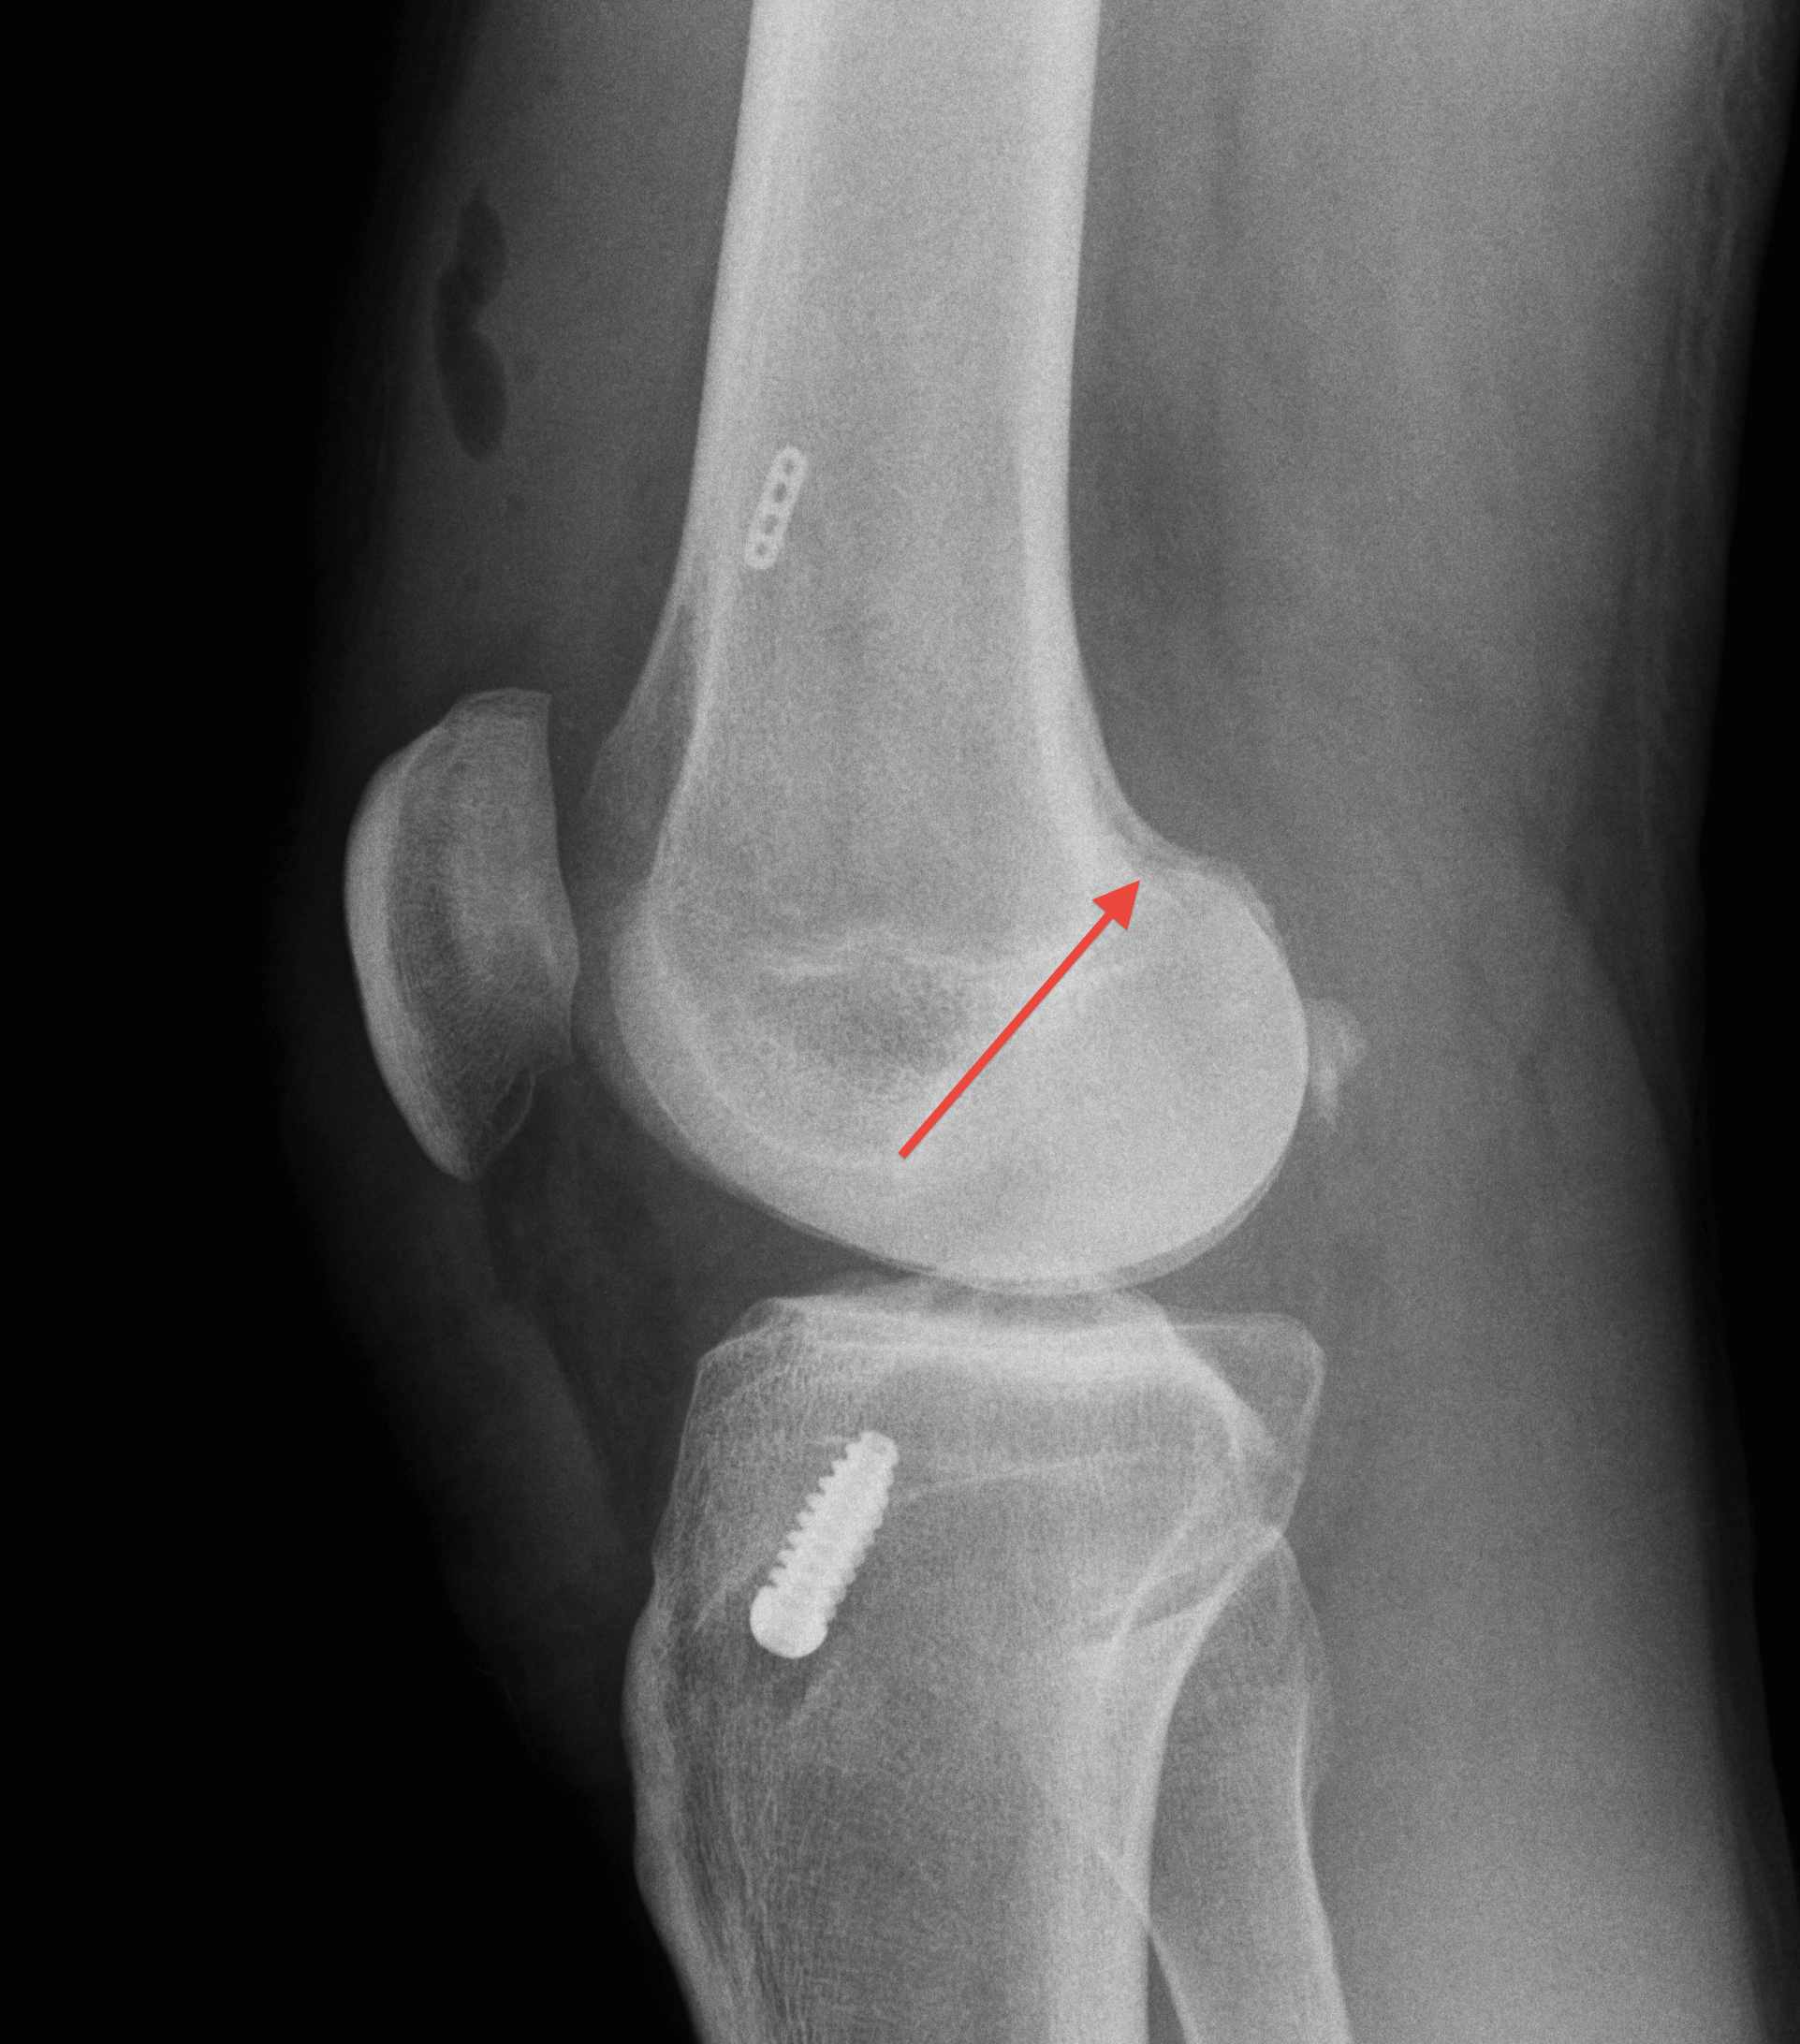

2. X-ray assessment

Lateral x-ray

Femoral tunnel

- intersection of line posterior femoral cortex and Blumensaat's line

Tibial tunnel

- posterior to Blumensaat's line in full extension

- parallel to Blumensaat's line

Pinczewski JBJS Br 2008

- 200 patients followed up over 7 years

1. Posterior femoral tunnel placement

- 86% along Blumensaat's line

2. Anterior tibia tunnel placement

- 48% along tibial plateau

- parallel to Blumensaat's